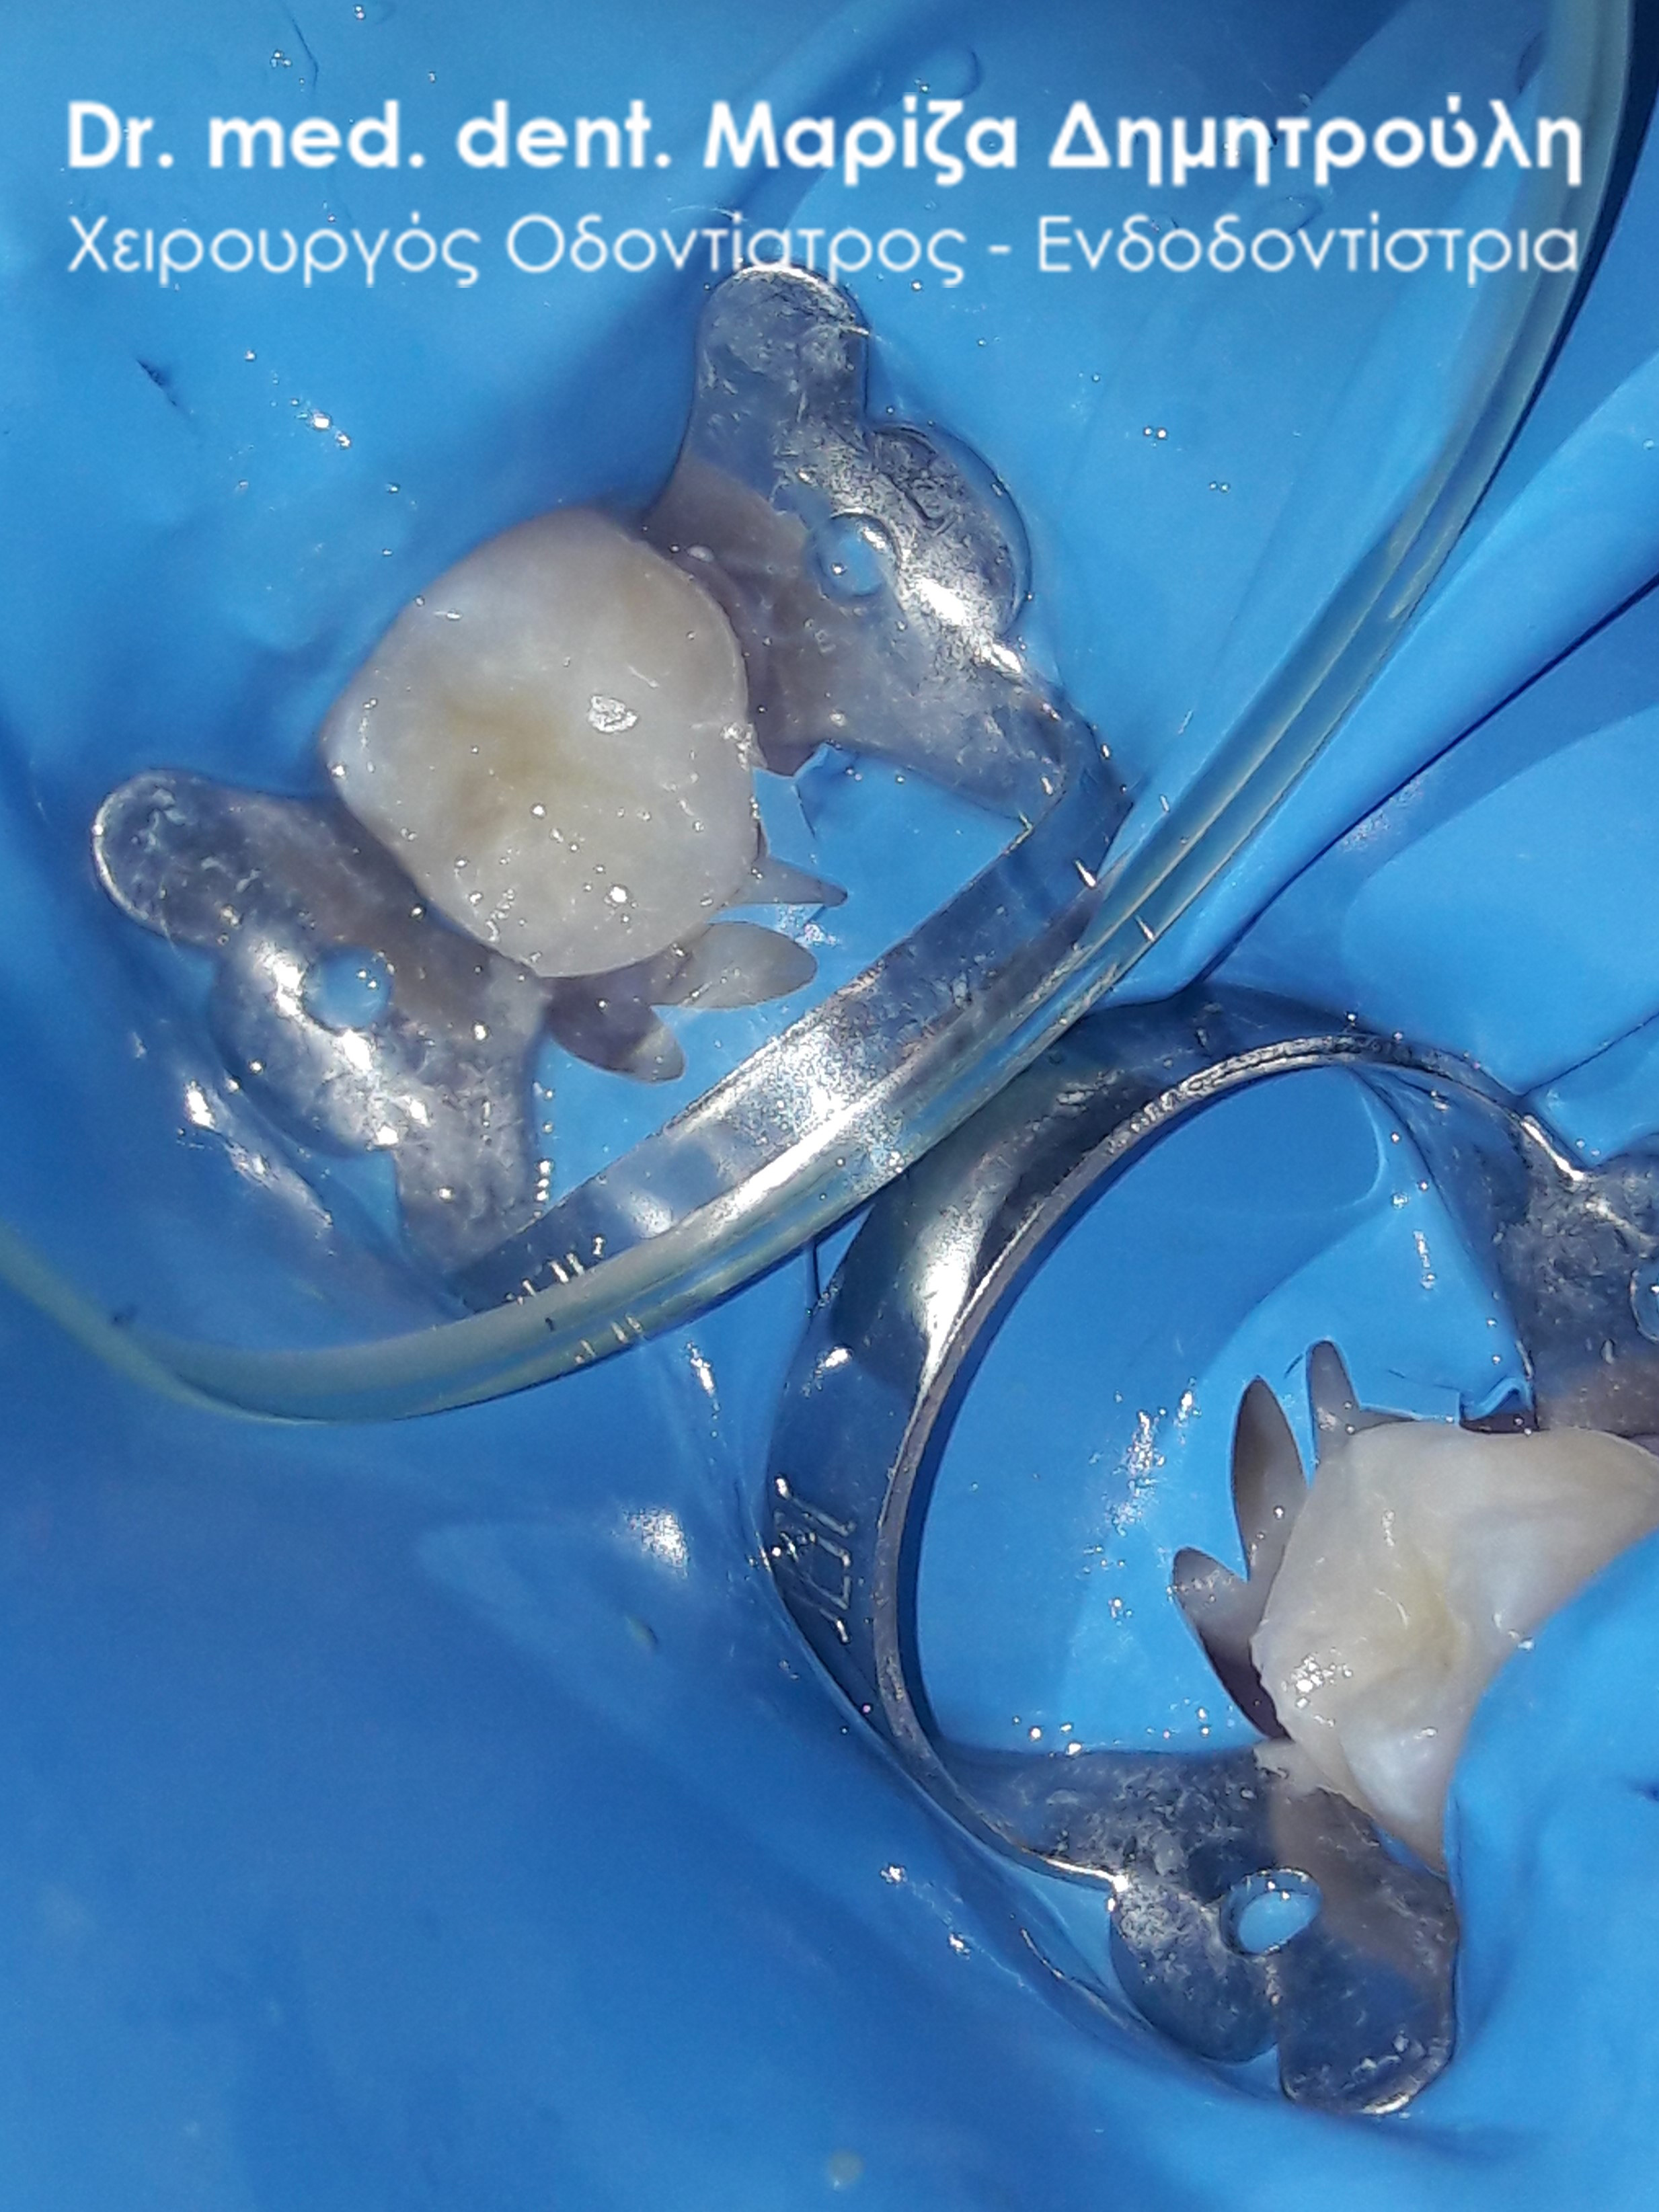

Περιστατικό – Σφράγισμα παιδικού δοντιού

Ο μικρός ασθενής επισκέφτηκε το ιατρείο για την αποκατάσταση του τερηδονισμένου παιδικού δοντιού του. Η ανασύσταση πραγματοποιήθηκε με λευκό σφράγισμα σύνθετης ρητίνης με τη χρήση του απομονωτήρα.

ΠΡΙΝ

Η κοιλότητα του δοντιού καθαρή μετά την αφαίρεση της τερηδόνας

ΜΕΤΑ